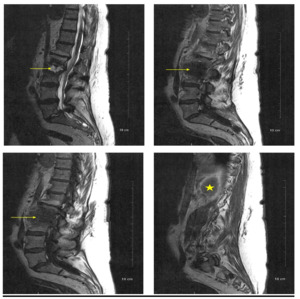

A lumbar spine MRI with and without IV contrast was obtained and revealed a low-density collection with peripheral heterogeneous and enhancement in the right psoas muscle measuring approximately 3cm by 1.5 cm extending to the right from the L2-L3 disk space (Figure 1). A subtle lucency along the inferior endplate of L2, suggestive of a developing fracture line, was also noted. The central canal of the L2-L3 space demonstrates moderate central canal stenosis. Also noted was an additional abscess more inferior to the original abscess. There was also a suggestion of septic synovitis of the posterior facets from L2 to L4 (Figure 2). Moderate hydro ureteral nephrosis was still present on the left. The left psoas muscle was normal.